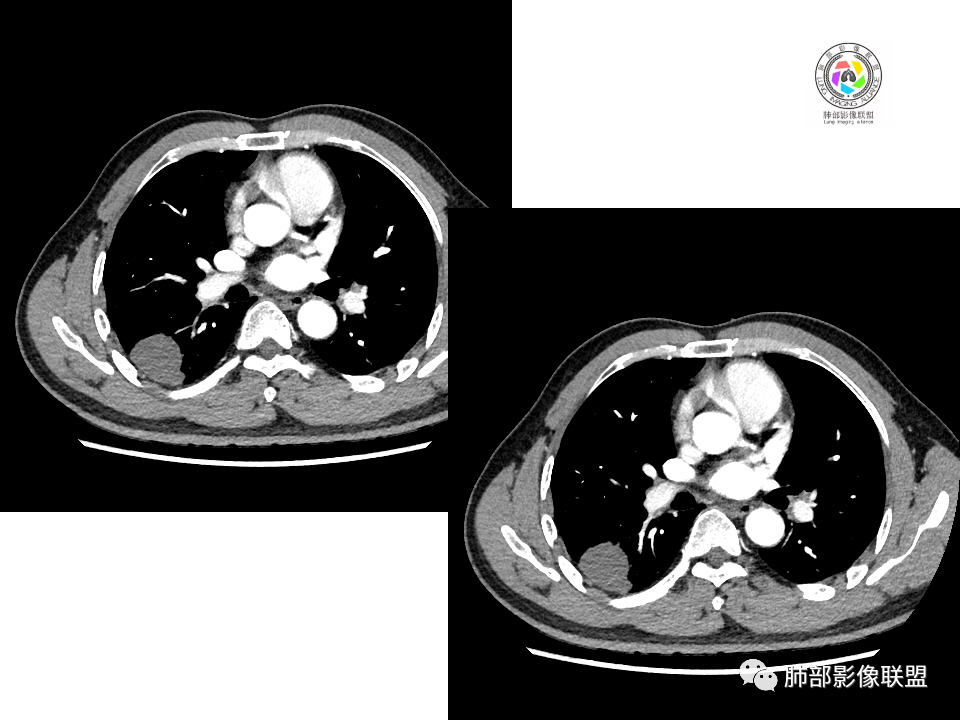

右肺下叶占位,胸膜下,与胸膜关系密切;

密度均匀;糊墙,边缘膨隆为主;

部分血管推移。

血管也是稍推移,在边缘,病灶密度均匀,边缘稍收缩;均匀强化;

这两个病灶的密度、强化、形态、边缘、与血管的关系类似;还是一元论吧。

2.右肺下叶背段胸膜下块影,边界清楚光整,上下极见磨玻璃晕,未见明显分叶毛刺和棘状突起,未见胸膜凹陷或胸壁侵入。密度均匀,轻度不均匀强化。未见支气管进入。

1.边缘光整干净,大病灶缺乏坏死等,不符合鳞癌影像学特征。尽管有吸烟史,还是偏年轻。

2.边缘光整,会是小细胞癌或是大细胞癌吗?小细胞癌的肺门纵隔淋巴结增大往往十分夸张,该患者不符合。

注意,基底段支气管血管束旁的小结节影,即便是淋巴结,也与背段病灶引流途径不符。

4.良性占位绕不过去,如发生于该部位的孤立性纤维瘤等……

病灶不均匀强化可以将含液支气管囊肿排除在外。

5.慢性感染灶。缺乏临床表现,强化不显著会想到继发性肺结核,背段病灶过于光整均匀,周边过于干净使人狐疑,且“成掎角之势”的中叶病灶结核灶特点也着实不多。

有老师分析,多发病灶有磨玻璃晕,可以符合隐球菌感染,确实如此。但背段边缘如此锐利的块影还是更容易让人联想到新生物。